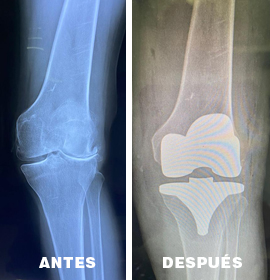

La artroplastia de reemplazo, o cirugía de reemplazo articular , es un procedimiento quirúrgico el cual consiste en sustituir una superficie articular artrítica o disfuncional por edad o por enfermedades que afectan a dicha articulación por una prótesis ortopédica.

El reemplazo articular se considera una opción cuando el dolor o la disfunción de la articulación es severo brindándole al paciente una nueva oportunidad de calidad de vida.

Procedimiento quirúrgico el cual consiste en sustituir una superficie articular artrítica o disfuncional por edad o por enfermedades que afectan a dicha articulación por una prótesis ortopédica.